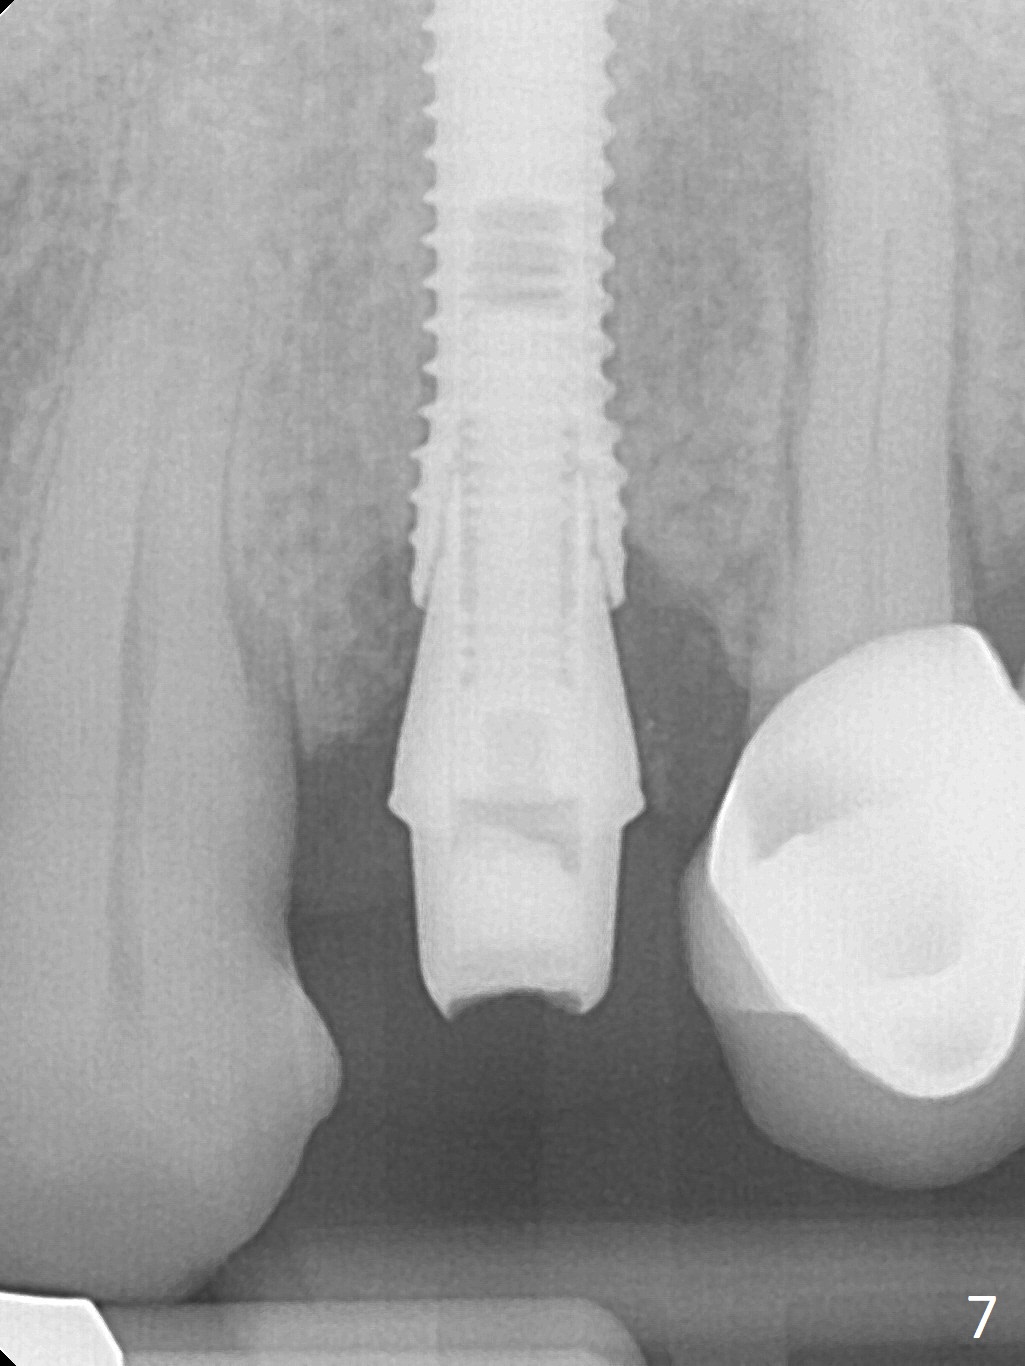

RPD Clearance